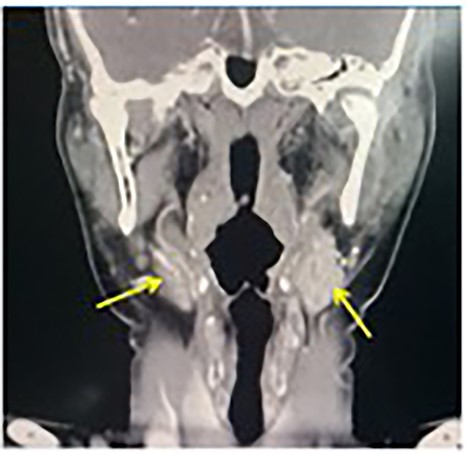

A contrast-enhanced computerized tomography (CECT) of the neck showed bilateral enhancing mass at the both carotid bulbs (Fig. 1), sandwiched between the external carotid artery (ECA) and the internal carotid artery (ICA) giving a positive Lyre sign. The CECT showed the left and the right mass measuring 3 × 2.5 cm and 2 × 1.2 cm, respectively (Fig. 2). No signs of thrombosis were seen. A two-staged excision was decided by the vascular surgeons and the surgical approach is described as the following.